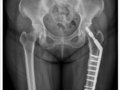

新型骨板 锁定骨松粉碎性骨折

国人骨质疏松问题日益严重,因骨质疏松引发的骨折,不仅患者本身难以察觉,而且也无法使用传统的骨钉骨板固定,治疗之路困难重重。新光医院发表一项最新技 术,以“锁定式骨板微创手术”的方式,治疗骨质疏松引发的“粉碎性骨折”,能加速骨骼愈合,大幅降低住院时间,造福广大骨质疏松症患者。

为了因应老人医学与相关健康议题,第二十届吴火狮纪念学术会议中,探讨骨质疏松症、骨质疏松骨折的特殊型态,以及治疗最新趋势。